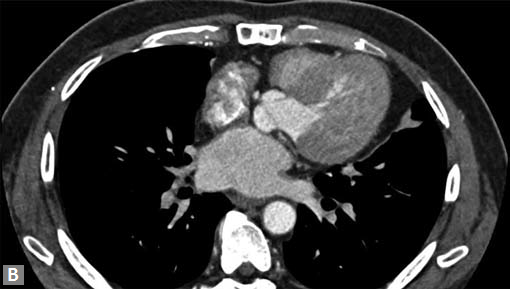

Filling defects (Figs 16A and B) may be seen in main

pulmonary artery (MPA), left pulmonary artery (LPA) and

right pulmonary artery (RPA), interlobar artery, segmental

divisions (Figs 17A and B). On occasions, detection in distal

parts of segmental divisions is difficult. This can be further

confounded by motion artifacts, non- or minimally opacified

accompanying pulmonary veins.